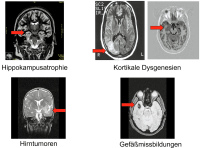

Abbildung 5: Strukturelle Befunde bei symptomatischen Epilepsien.

Keywords: EpilepsieMRTNeurologie